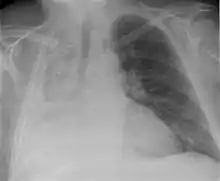

| Atelectasis of a person's right lung | |

Clinically significant atelectasis is generally visible on chest X-ray; findings can include lung opacification and/or loss of lung volume. Post-surgical atelectasis will be bibasal in pattern. Chest CT or bronchoscopy may be necessary if the cause of atelectasis is not clinically apparent. Direct signs of atelectasis include displacement of interlobar fissures and mobile structures within the thorax, overinflation of the unaffected ipsilateral lobe or contralateral lung, and opacification of the collapsed lobe. In addition to clinically significant findings on chest X-rays, patients may present with indirect signs and symptoms such as elevation of the diaphragm, shifting of the trachea, heart and mediastinum; displacement of the hilus and shifting granulomas.[10]